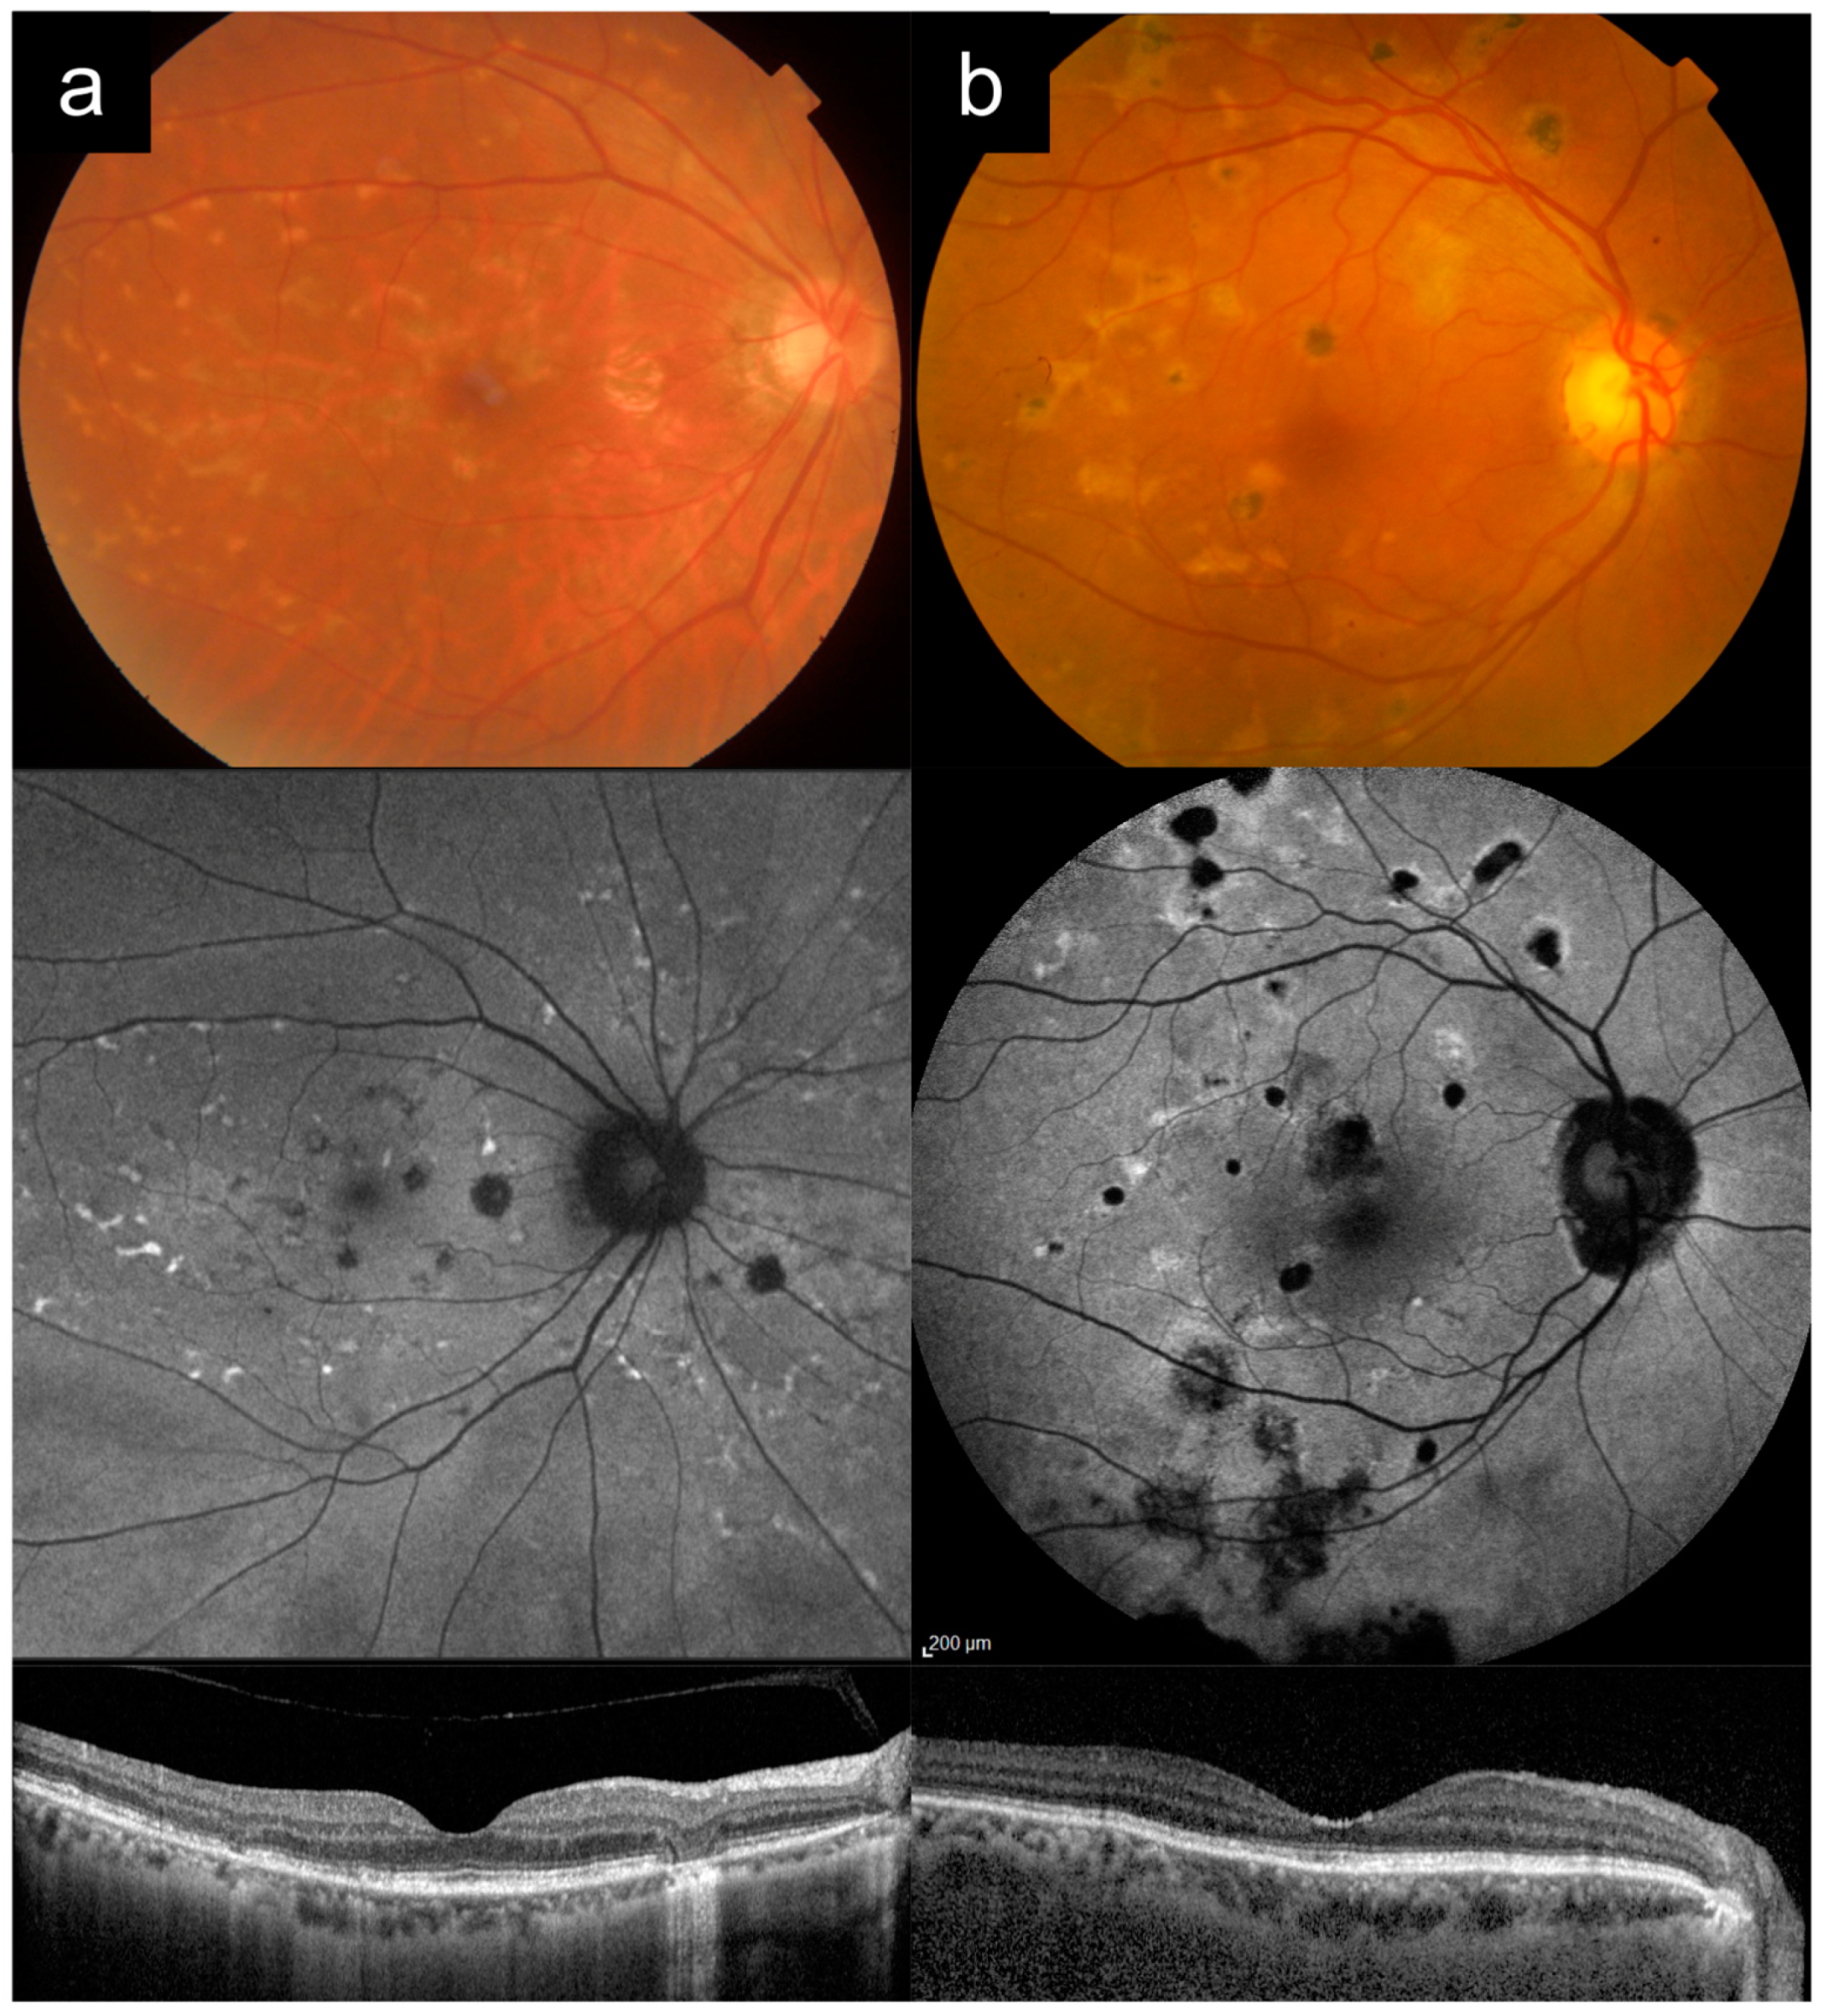

3.5. Cases 5a versus 5b: Severe, Early-Onset Stargardt Disease versus Late-Stage Retinitis Pigmentosa

Case 5a had bilateral blurring of vision and hemeralopia from around 16 years old. Later, in his 20 s, he also developed nyctalopia. He had two siblings who were similarly affected, and no other known family history, consistent with AR inheritance.

Figure 5a shows imaging of his right eye in his 60s. VA in the right eye was count fingers (CF) at the time. CFP imaging of the posterior pole shows widespread diffuse RPE and choroidal atrophy, with arteriolar attenuation and pigment clumps. UWF imaging better demonstrates that the pattern of RPE and choroidal atrophy is nummular, with confluence around the posterior pole. OCT imaging shows diffuse outer retinal, RPE, and choroidal atrophy. Genetic testing and segregation analysis revealed two causative

ABCA4 variants in trans (

Table 1).

Case 5b presented first with nyctalopia in his late teens. Nyctalopia, peripheral vision and eventually central vision worsened progressively. He had consanguineous parents, and no other affected members of the family.

Figure 5b shows imaging of the left eye from his 60s. VA in the left eye was hand motion (HM) at the time. CFP imaging shows widespread diffuse RPE atrophy with some possible narrow islands of relative sparing in the supertemporal macula, severe arteriolar attenuation, and bony spicule hyperpigmentation and clumps. UWF imaging shows that the atrophy is nummular and pan-fundal. OCT imaging shows diffuse outer retinal and RPE atrophy with choroidal thinning. Genetic testing analysis showed that this individual was homozygous for

REEP6 c.517+5G>T.

Cases of severe, early-onset Stargardt disease such as Case 5a can be frequently misdiagnosed as late-stage RP (or even choroideremia), based on widespread RPE and choroidal atrophy, arteriolar attenuation, and pigment clumping. Accurate clinical differentiation between these two entities can be helpful, as the genetic testing hypotheses for them are starkly different. An

ABCA4-RD phenotype is typically a single-gene hypothesis, whereas RP can be caused by a very large number of candidate genes. Useful distinguishing features between the two are: (1) the clinical history for

ABCA4-RD typically starts with central vision loss first and early in the disease process, whereas for advanced RP the presenting symptoms is nyctalopia and peripheral field loss, with central vision loss only late in the disease; (2) careful clinical examination (or UWF imaging) will usually show that

ABCA4-RD has a more central distribution (even in late-stage disease), with extensive macular involvement, and centrifugal disease progression, whereas RP has a centripetal progression [

24]; (3) peripapillary sparing, when present, points towards

ABCA4-RD. However, as Case 5a illustrates, this is not always present, and, in fact, peripapillary sparing has been reported to be absent in about 2 to 7% of cases [

25]; (4) pigment in

ABCA4-RD is typically more prevalent in larger round clumps, whereas, in RP, it is usually more elongated and bony spicule-like; (5) if the pedigree suggests an inheritance pattern other than AR, this points away from

ABCA4-RD, though one should always keep in mind the possibility of pseudo-dominant inheritance.